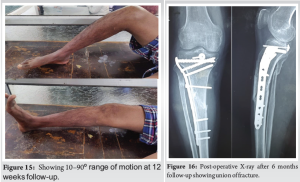

At 12 weeks after surgery, the ROM was 10–90o. The posterior drawer test showed no instability (Fig. 14 and 15).

At 6 months after surgery, the ROM was 0–120o. The posterior drawer test showed no instability. Patient was able to do straight leg raise and was able to walk without support. Lysholm knee score was 95 showing excellent result (Fig. 16 and 17).